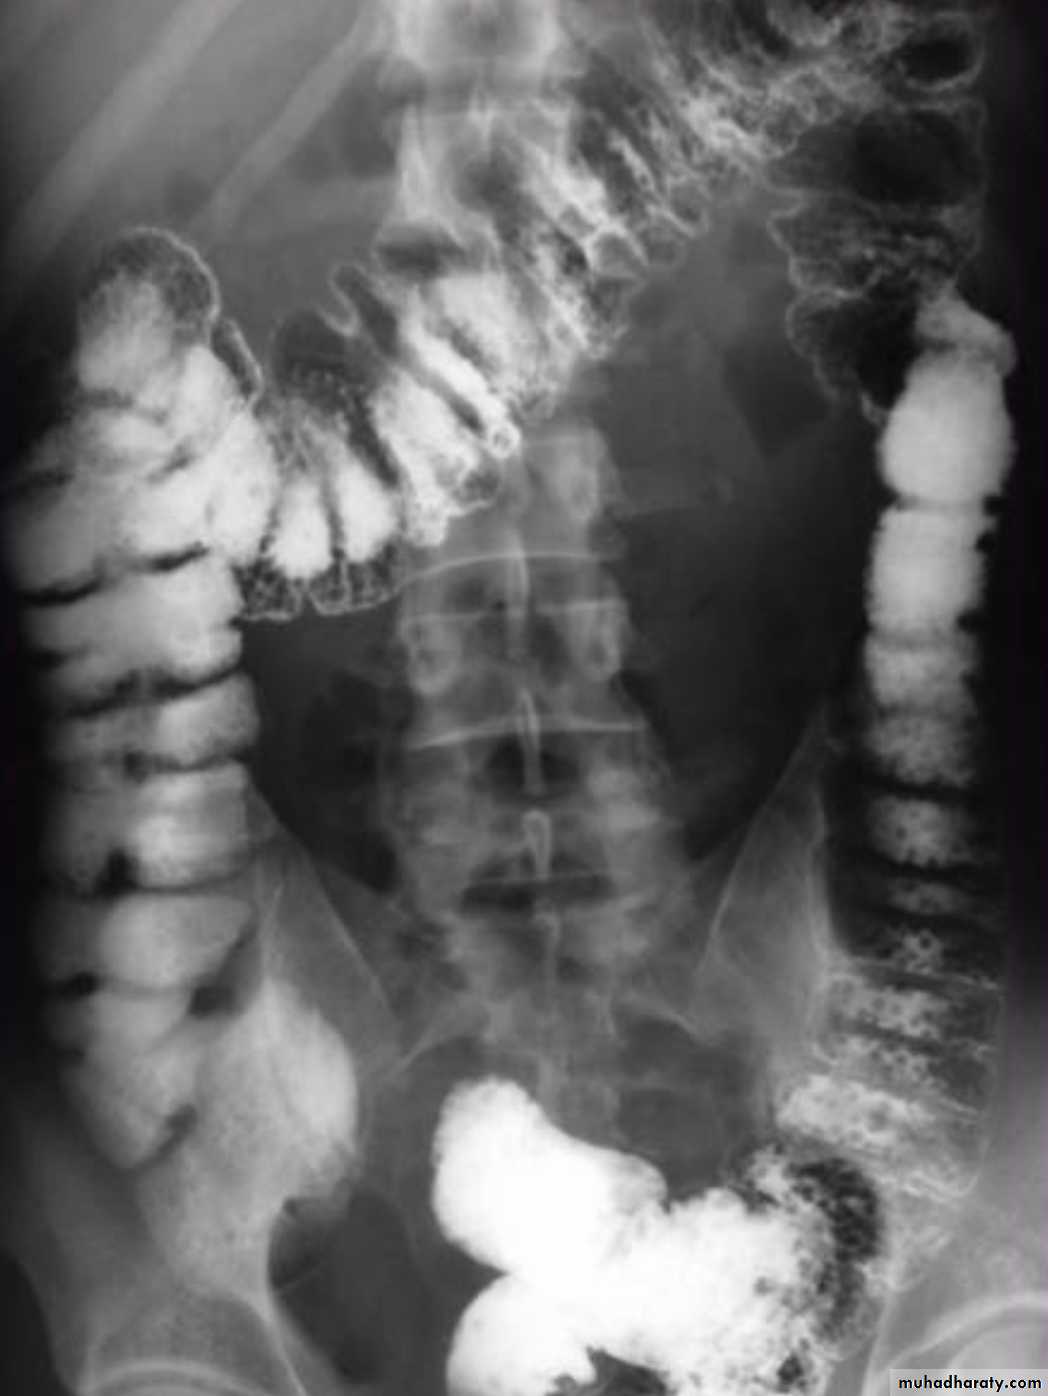

Colonic diverticulosis

refers to the presence of multiple diverticula. It is quite distinct from diverticulitis which describes inflammation and infection of one or multiple diverticula.Radiographic features

Diverticula range in size from a few millimeters to a few centimetersBarium enema

Both single and double contrast barium enemas are able to demonstrate diverticula as barium-filled out-pouchings.